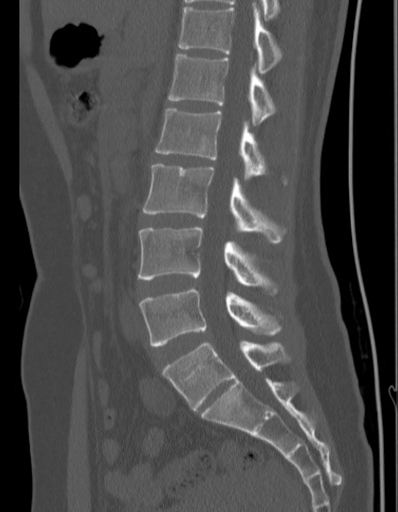

大多数情况下,这些变异是在进行腰部X线、CT或MRI检查时偶然发现的。常见的影像学特征包括:

骶椎腰化表现:

· 第一骶椎(S1)与其他骶椎间保留明显的椎间盘间隙

· S1横突发育不良或与骶骨翼未完全融合

· 第一骶椎与第二骶椎间可见明显的关节间隙

腰椎骶化表现:

· 第五腰椎(L5)横突增大并与骶骨形成骨性连接

· L5与S1椎间盘退化或消失

· L5部分或完全与骶骨融合